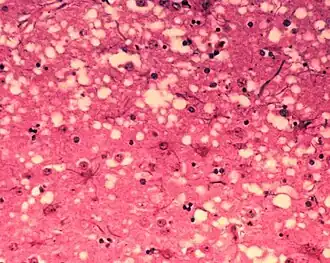

Boviene spongiforme encefalopathie (BSE), ook wel gekkekoeienziekte genoemd, is een ziekte van runderen die door prionen wordt veroorzaakt. De ziekte ontleent zijn naam (die sponsachtige hersenziekte bij runderen betekent) aan het uiterlijk van het hersenweefsel onder de microscoop: de dode, verdwenen zenuwcellen laten 'leegten' achter.